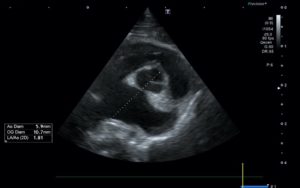

Echo 3

Par le Dr M. Pic